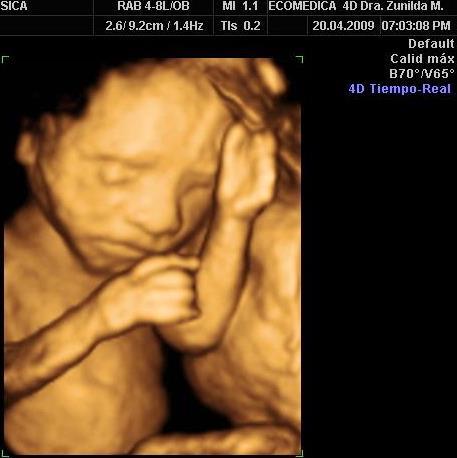

776 Followers 700 FollowingActualpacs is a cloud platform for radiologists and imaging centers to improve their productivity and efficiency in medical images and reports management